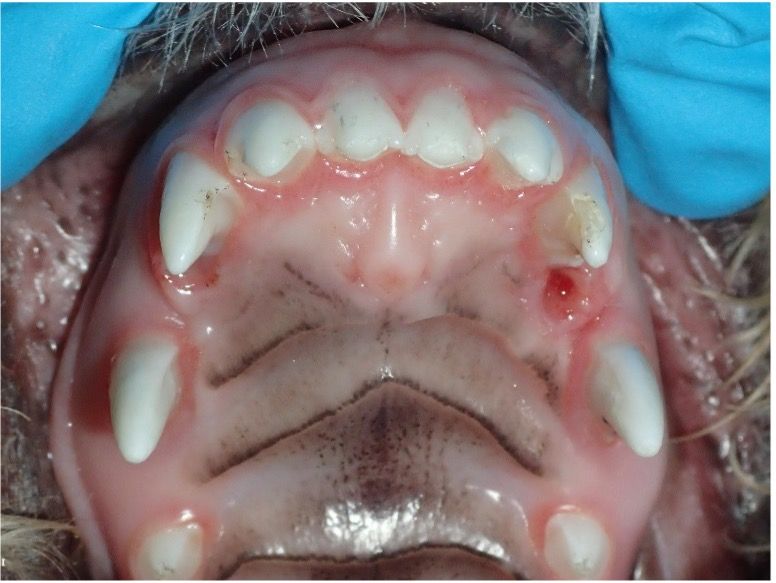

• Poodles and doodles: These breeds can have linguoversion of mandibular canine teeth (Figure 9), also known as base narrow, which often causes occlusal trauma on the roof of the mouth (Figure 10). Early intervention during deciduous and adult tooth stages is crucial.

• Shetland sheepdogs are prone to rostroversion of maxillary canine teeth (Figure 11), sometimes requiring orthodontic treatment if causing oral trauma.